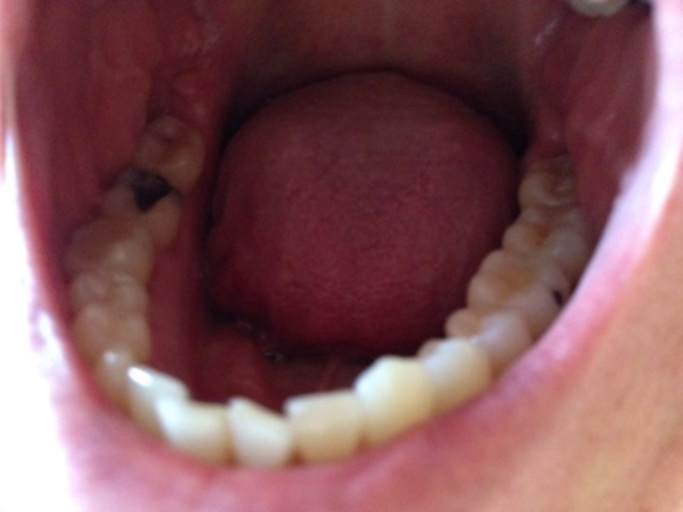

I had a composite filling on my molar tooth in the top row a couple weeks ago. But yesterday, I found my tongue lingering on that tooth, so I checked it out in the mirror, and it appears that a hole has appeared in my filling! It wasn't on the natural part of the tooth, but the filling. It was on the front, and it's quite a big hole, if I'm going to be honest with you, and I'm not very sure, but it seems to have appeared overnight or something. I flick my tongue in my mouth a lot, and I didn't feel anything 'unusual' in my teeth before. It might be that it already existed before, but I didn't notice, though. It doesn't hurt either, but I am still quite concerned. Did the filling break down or do I have a cavity again? I brush very carefully 2 times a day, for more than two minutes. I use mouthwash two hours after brushing at night and floss once a day. I use an electrical toothbrush. If it is a cavity, am I doing anything wrong with my oral hygiene routine? I'm very sorry about the blurry picture! It's not clear, but I hope you can see that there's a hole in the right molar tooth when it's compared to the one at the left side. There should be something covering the front up in the right molar tooth, but the whole chunk of that is gone. I'm also very sorry for the long text, but thank you to the people who read this to the end and to the answers in advance, too.(And if you are wondering why I have such little teeth in the picture, I have a genetic condition where my teeth doesn't grow back after it's baby version fell.)